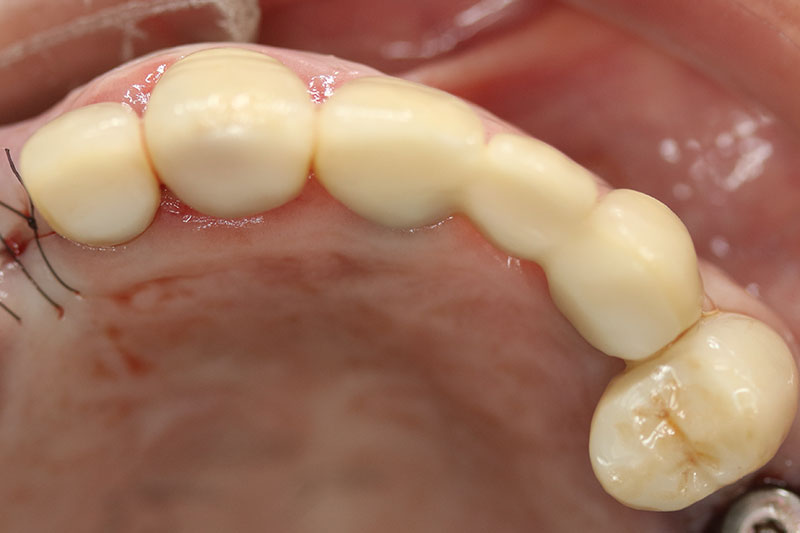

缺牙多顆

案例一

術後